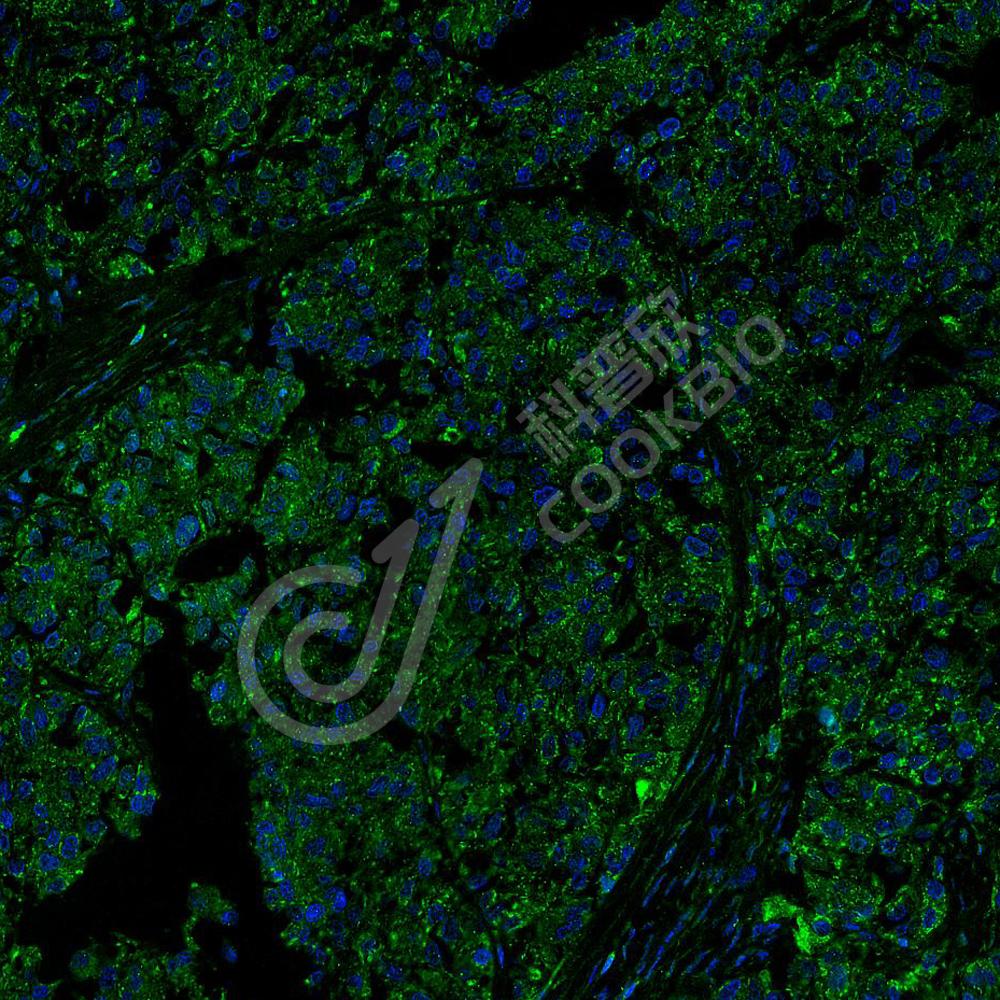

图像

IHC检测ATF-4蛋白(货号 K1333411).

样品: 小鼠小肠, 4%多聚甲醛 (货号KSG1101) 固定12-24小时.

抗原修复: 柠檬酸抗原修复液(干粉, pH 6.0) (KSG1201), 98℃, 20分钟.

—抗: 1: 2300稀释, 4℃ 孵育过夜.

二抗: S-vision免疫组化多聚二抗(山羊抗兔),即用型 (货号KB3906), 室温孵育20分钟.